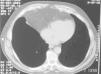

Hernia diafragmática de Morgagni en el adulto

Diaphragmatic hernia of Morgagni in the adult